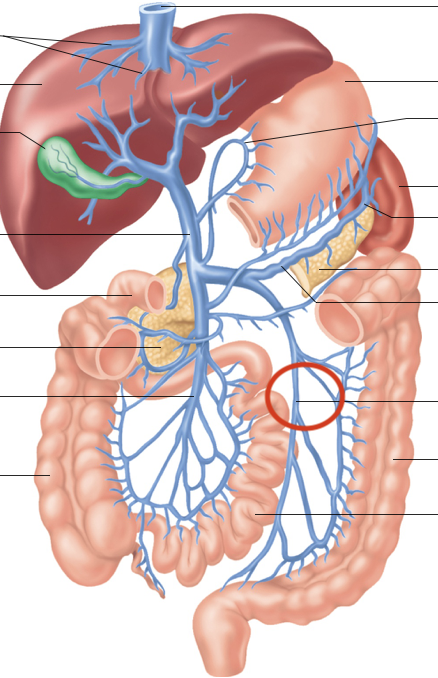

Hepatic Portal System (illustration)

hepatic portal vein

superior mesenteric-small intestine, first half colon

gastric-stomach

splenic-spleen and pancreas

inferior mesenteric-second half colon

hepatic veins